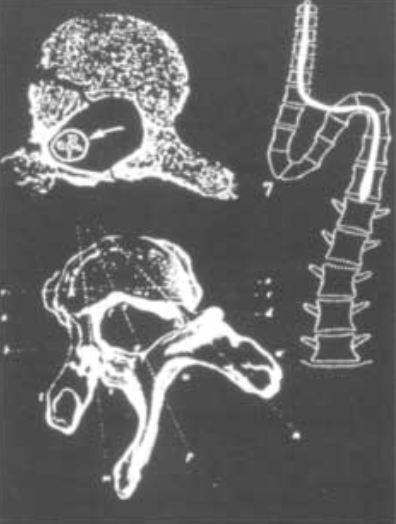

Se trata de la herniación en sentido caudal de las amígdalas cerebelosas y del tejido cerebeloso en el canal cervical (Fig. nº 2). Puede producir una dificultad en el drenaje del líquido cefalorraquídeo a través del techo del IVº ventrículo que se deforma al ser arrastrado caudalmente. En casos extremos puede producir hidrocefalia.

En casos extremos de pacientes con ESCID se ha observado un efecto lítico y cavitario e incluso salida extravertebral de la médula espinal (Fig. nº 2). El componente lateral de la FTM es tan importante en estos pacientes que la médula puede ejercer una presión desde el interior del canal vertebral llegando a atraversar los pedículos vertebrales del lado cóncavo.

Figura nº 3. Imagen de una escoliosis severa. La médula a tensión ha producido una lisis del canal óseo. Esquema de Roth M. [3] citada por el Dr. Royo-Salvador. Se basa en una aportación de Hamilton, J. J. y de Schmidt, A. C. [8]